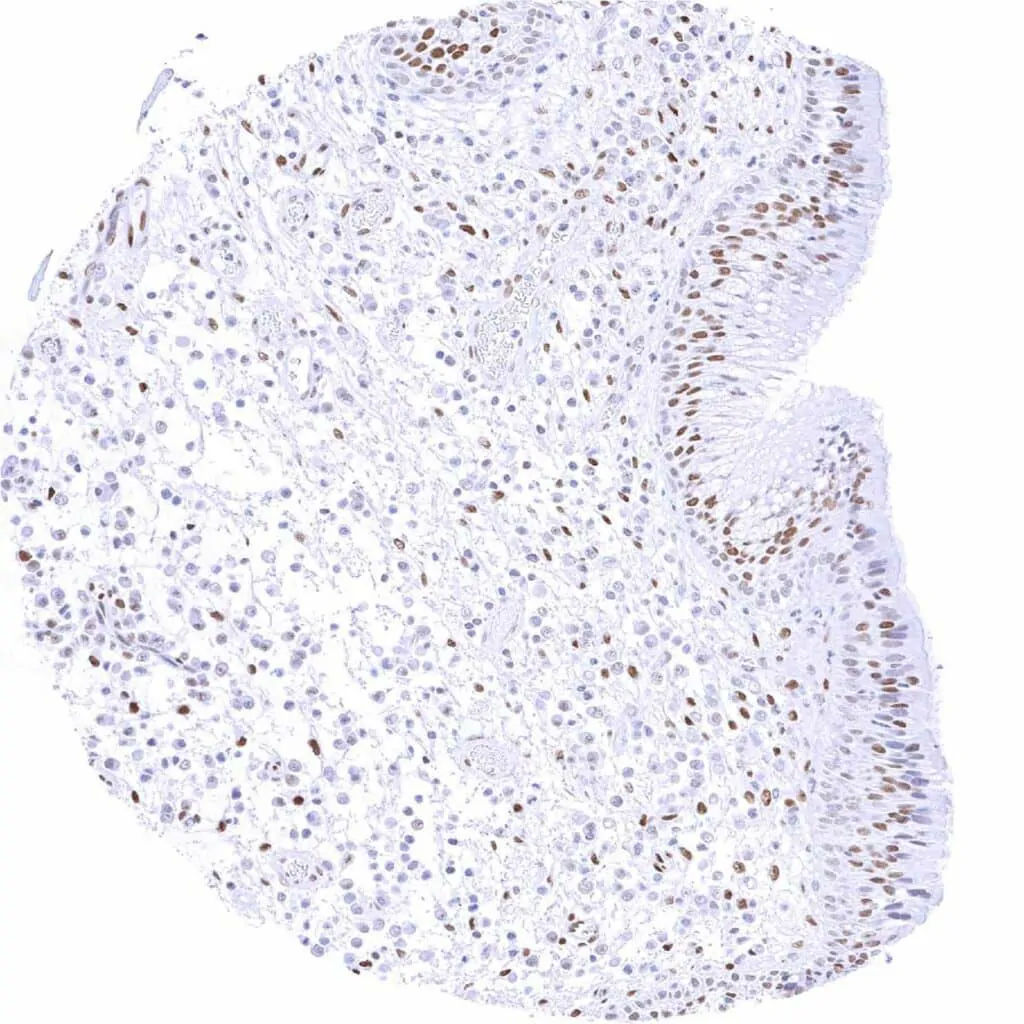

Uterus, endometrium (proliferation) – Moderate to strong TLE1 staining of epithelial and stromal cells